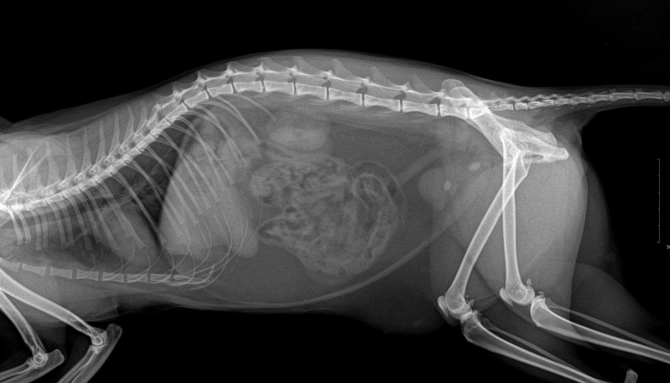

診斷膀胱結石通常需要影像學檢查。X光能顯示鈣化結石,但有些結石(如尿酸結石)在X光下不顯影,這時超音波就派上用場。尿液分析則可檢測pH值、結晶和感染。

我的狗狗阿福,8歲米克斯,去年發現膀胱結石約0.8公分。獸醫建議開刀,但我決定先嘗試非手術方法。以下是具體步驟:

六個月後,結石縮小到0.3公分,症狀消失。這過程花了約1.5萬新台幣(檢查和飼料),比手術便宜。但並非所有狗狗都適用,阿福的結石是磷酸銨鎂類型,較易溶解。